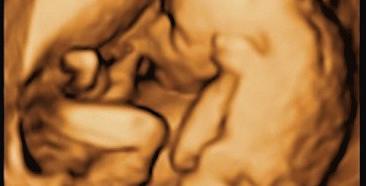

MS is a chronic autoimmune disease of the central nervous system, the MS Society of Canada website explained. Since that includes the brain, spinal cord and optic nerve, MS can affect vision, memory, balance and mobility. It is considered an episodic disability meaning that the severity and duration of illness and disability can vary and are often followed by periods of wellness. It can also be progressive.

MS attacks myelin, the protective covering of the nerves, causing inflammation and often damaging the myelin, the MS Society of Canada website said.

Myelin is necessary for the transmission of nerve impulses through nerve fibres.

If damage to myelin is slight, nerve impulses travel with minor interruptions; however, if damage is substantial and if scar tissue replaces the myelin, nerve impulses may be completely disrupted, and the nerve fibres themselves can be damaged.

MS is unpredictable and may cause symptoms such as extreme fatigue, lack of coordination, weakness, tingling, impaired sensation, vision problems, bladder problems, cognitive impairment and mood changes.